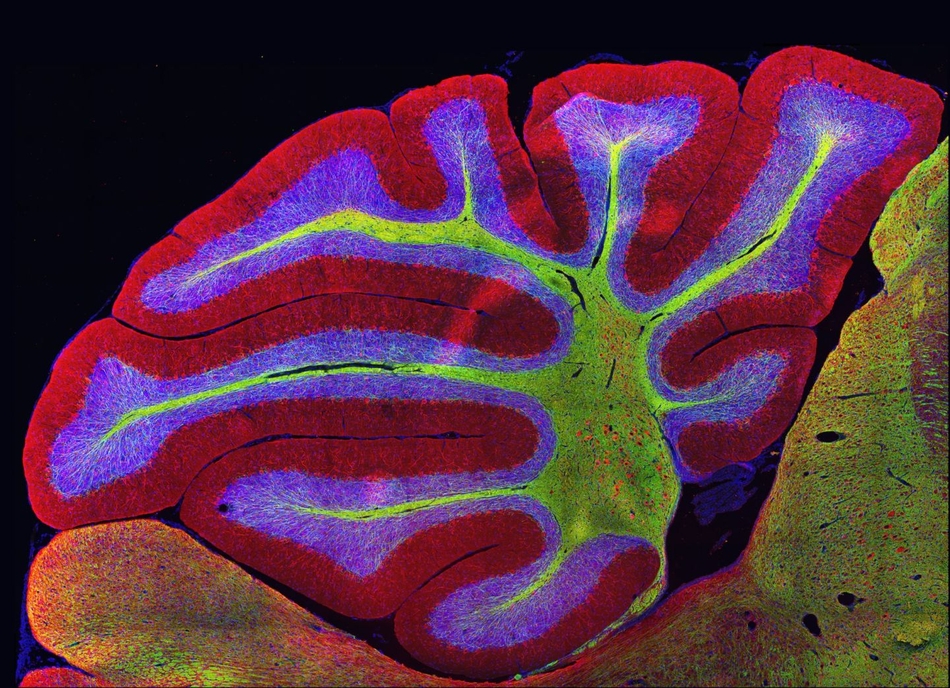

图为小鼠的小脑.脊椎动物均拥有该结构,负责控制肌肉运动.